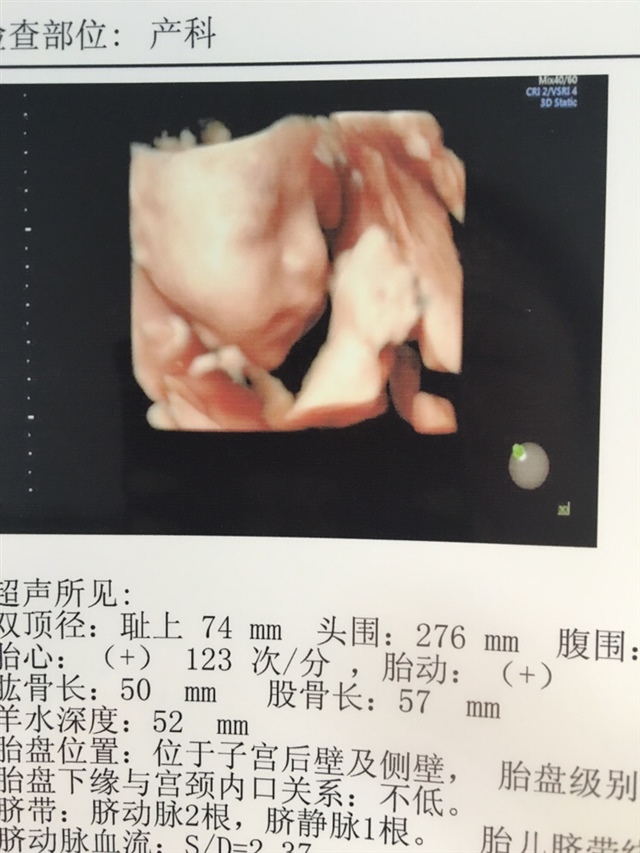

长得太好看了,希望我到时候四维也能有这么清晰

A洋洋👶💗[帖主]:嗯现在四维都特别清晰22周以后就差不多了

A洋洋👶💗[帖主]:22周到24周最佳时间,我的有点晚了28周做的